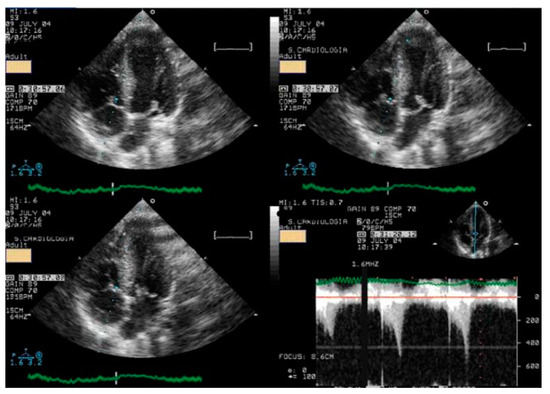

We read with interest the excellent review manuscript from Huang, S.-W. and Liu, Y.-K. [1], which describes that pediatric chest pain is a common chief complaint in the emergency department. Not surprisingly, children with chest pain are usually brought to the emergency department by their parents out of fear of heart disease. However, chest pain in the pediatric population is generally a benign disease. In this review, we have identified musculoskeletal pain as the most prevalent etiology of chest pain in the pediatric population, accounting for 38.7–86.3% of cases, followed by pulmonary (1.8–12.8%), gastrointestinal (0.3–9.3%), psychogenic (5.1–83.6%), and cardiac chest pain (0.3–8.0%). Various diagnostic procedures for cardiac chest pain are commonly used in the emergency department, including electrocardiogram (ECG), chest radiography, cardiac troponin examination, and echocardiography. However, these examinations demonstrate limited sensitivity in identifying cardiac etiologies, with sensitivities ranging from 0 to 17.8% for ECG and 11.0 to 17.2% for chest radiography. To avoid the overuse of these diagnostic tools, a well-designed standardized algorithm for pediatric chest pain could decrease unnecessary examination without missing severe diseases [2,3,4]. Our primary concern is that no attention has been given to exercise-induced intraventricular gradients, which are easily detectable using exercise stress echocardiography and have been associated with chest pain and other symptoms [5,6,7,8,9,10,11,12,13], including in children. We present the case of a 15-year-old boy, a rugby player, who experienced severe chest pain followed by syncope during a match. Upon evaluation at the emergency department, he showed a significant increase in troponin levels. Coronary angiography (Figure 1) and CT angiography (Figure 2) revealed normal results. However, an exercise stress echocardiogram identified a significant intraventricular gradient (Figure 3).

Figure 1. Normal coronary angiography.